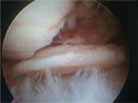

CHIRURGIA ARTROSCOPICA: ginocchio, caviglia e spalla, ricostruzione del Legamento Crociato Anteriore del ginocchio.